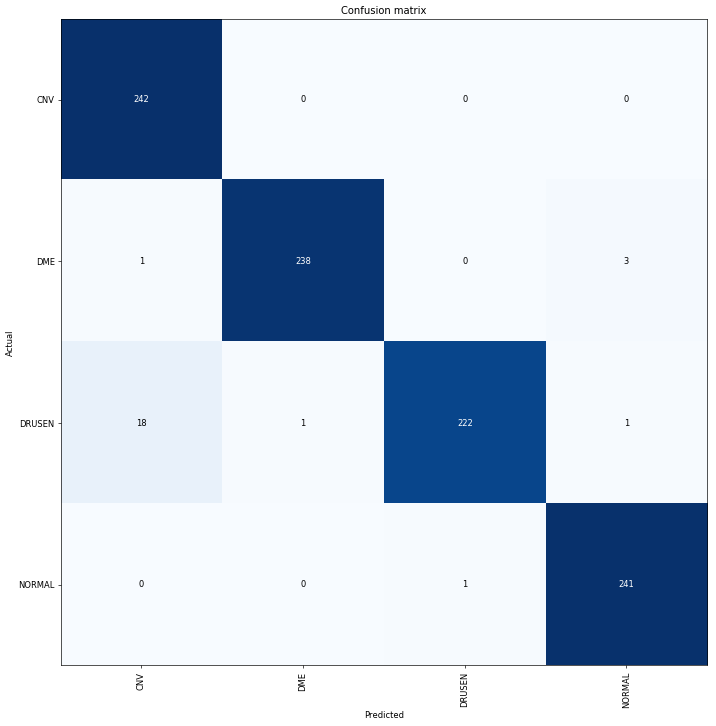

learn.save('stage-1')97% before fine-tuning? That’s not a bad start. How does our confusion matrix look? The biggest difficulty the model is having is between Drussen and CNV, which is the same confusion that was most common in the human pathologists, an encouraging sign.

interp = ClassificationInterpretation.from_learner(learn)

losses,idxs = interp.top_losses()

We can get ~99% accuracy using the same dataset as Kermany et. al. with the fast.ai workflow, even for a seemingly complex problem like retinal pathology. The model in the paper is ~96% accurate and the best human pathologist was in the 99% range, so we’re definitely in good company with this result.